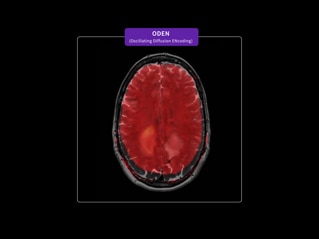

Enabling personalized oncology treatment with MRI

Our goal is to help you personalize cancer diagnosis, radiation therapy planning and treatment assessment for every patient. To achieve this, we can provide advanced functional and metabolic imaging information with SIGNA™ PET/MR AIR™⁵ and ODEN* (Oscillating Diffusion Encoding). Our AIR™ RT Suite solution is easy to set up and helps ensure the proper positioning of each patient. And the 32-channel AIR™ Open Coils provide patient comfort while delivering a high signal-to-noise ratio.

*SIGNA™ MAGNUS and ODEN are 510(k) cleared with the FDA. Not yet CE Marked. Not available for sale in all regions.